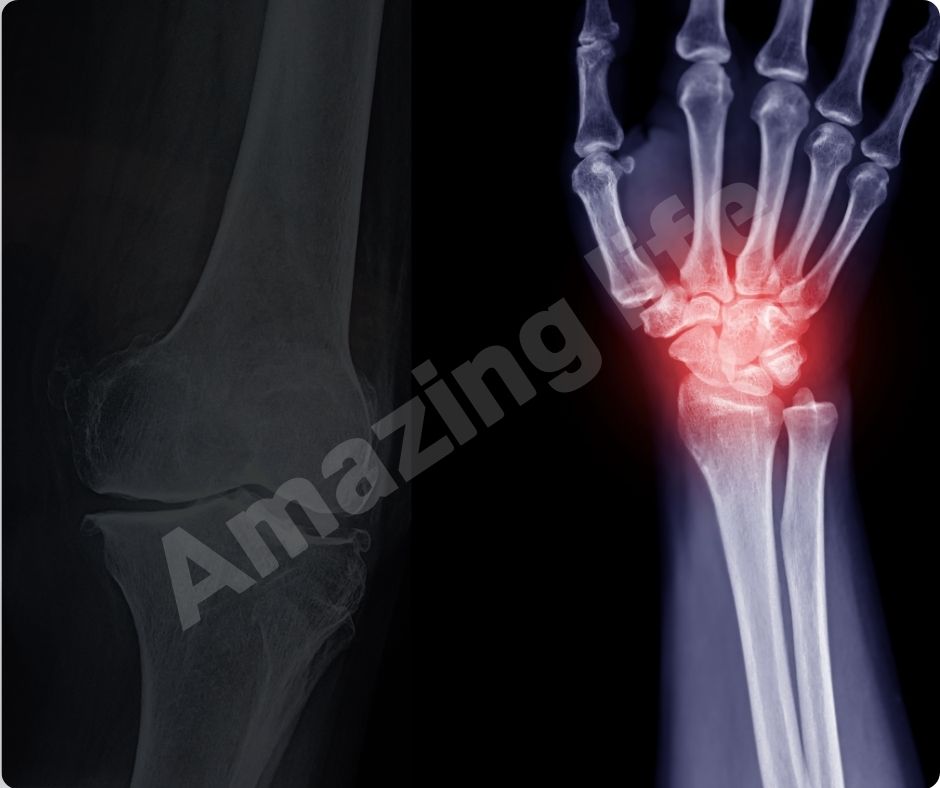

많은 연구에서 글루코사민의 효능이 관절 통증을 완화하는 데 효과적이라는 결과가 나왔습니다. 최근 연구에 따르면, 글루코사민과 콘드로이틴 보충제를 꾸준히 섭취하면 심혈관 질환 사망률이 65%까지 감소할 수 있습니다.

염증 감소

글루코사민의 효능은 염증을 감소시키는 데도 효과적입니다. 관절염은 염증으로 인해 발생하는 경우가 많으므로, 글루코사민을 통해 염증을 줄이면 관절염 증상을 완화할 수 있습니다. 이는 자연적인 방법으로 관절 건강을 유지하는 데 유용합니다.